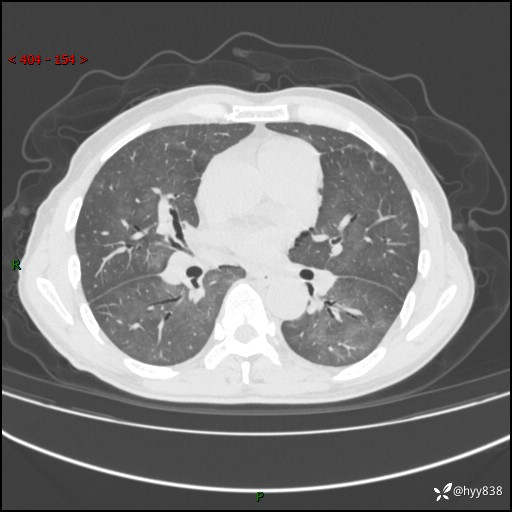

肺结节入院,CT却发现肺部弥漫性病变,what happened---(有结果)

辅助检查:CT

胸部CT平扫

不是讨论肺部结节